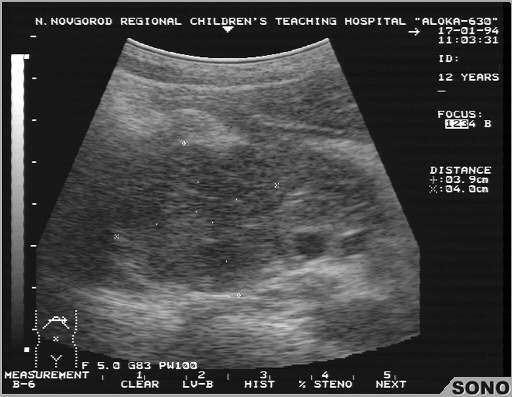

Муковисцидоз